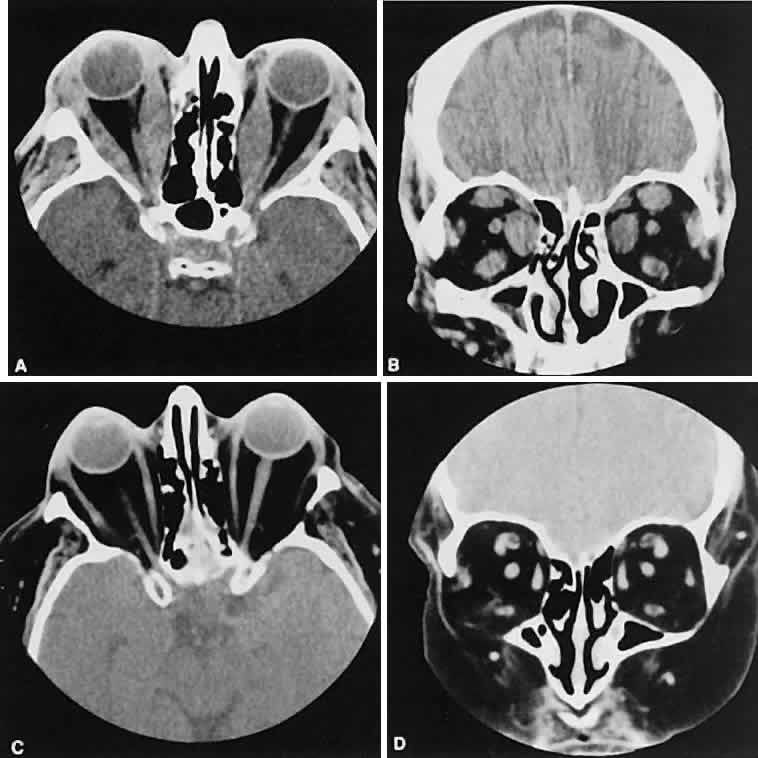

Graves' orbitopathy probably represents the most frequent cause of proptosis and EOM enlargement. The CT findings are fairly stereotyped and typically display various degrees of EOM enlargement (Fig. 7). The inferior rectus muscle usually is affected earliest, followed by the medial rectus, superior rectus, and finally the lateral rectus muscle. Rootman and colleagues13 noted more frequent involvement of the superior rectus/levator and medial rectus muscles than what had been reported previously with Graves' orbitopathy. These muscles can be affected in isolation, with the exception of the lateral rectus. To the best of our knowledge, isolated lateral rectus enlargement has not been reported in Graves' orbitopathy and in our experience usually is associated with a sphenoid wing meningioma.

Fig. 7. Graves' orbitopathy with two variations. Axial (A) and coronal (B) views show symmetric fusiform enlargement of the extraocular muscles with tapered muscle insertions. Note the predominant enlargement of the inferior, medial, and superior rectus muscles with lesser involvement of the lateral rectus muscle, a frequent pattern of enlargement in Graves' orbitopathy. Axial (C) and coronal (D) views of Graves' orbitopathy with expansion of retrobulbar ground substance and relative sparing of the extraocular muscles.